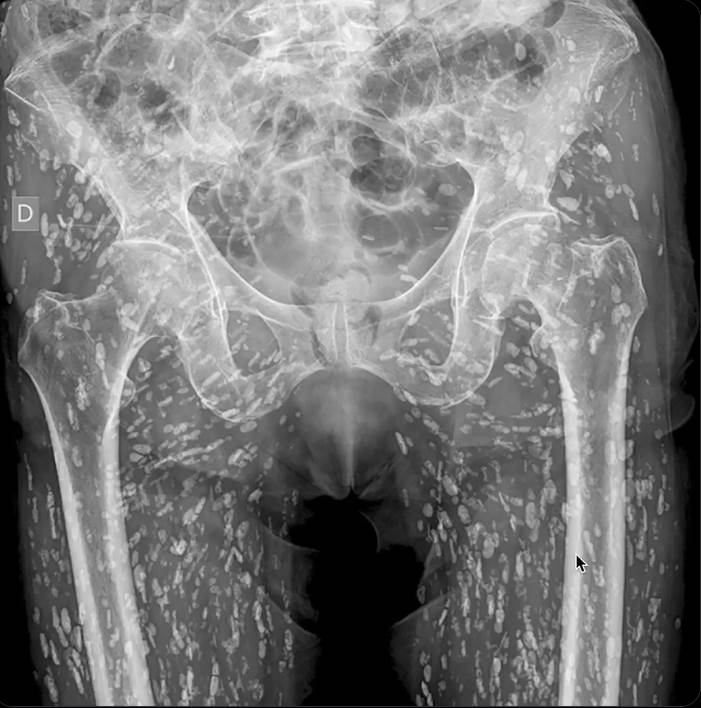

根據《每日星報》報導,醫療專業人士薩姆·加利(Sam Ghali)近日在社群X上分享了這張X光片,並表示這是他見過「最瘋狂的X光片」。從影像中可見,有密密麻麻的白點分佈在患者骨盆周圍,那就是已鈣化的豬肉絛蟲卵,場景令人不寒而慄。

加利進一步解釋,豬囊尾蚴病是因豬肉絛蟲的幼蟲進入人體後引起的,這些幼蟲能透過血液循環擴散至全身,尤其偏好寄生在臀部、腿部的肌肉與軟組織中。他指出,當寄生蟲只存在於骨盆等部位時,雖然對生命威脅有限,但若幼蟲侵入大腦,情況將變得極其危險。

「一旦幼蟲進入中樞神經系統,患者可能會出現頭痛、癲癇發作、精神混亂等症狀,甚至可能導致死亡。」加利警告,豬囊尾蚴病的神經性併發症不容忽視,並強調預防的關鍵在於避免食用未煮熟或生豬肉。